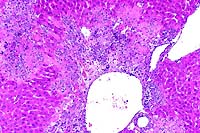

10x

obj

- Case 15-2. Seminal vesicle. The submucosa is heavily

infiltrated by pleomorphic epithelial cells. Both mucosal papillary

fronds and submucosa have an abundant inflammatory (neutrophilic)

infiltrate.

40x

- Case 15-2. Seminal vesicle. Pleomorphic tumor cells,

which are admixed with neutrophils in the submucosa may contain

multiple nuclei or variably sized vacuoles which displace the

nucleus peripherally (signet ring cells).

- AFIP Diagnosis: Seminal vesicle: Adenocarcinoma, Crl:CDâ(SD)Br

rat, rodent.

- Conference Note: Replacing most of the normal glandular

parenchyma and compressing the adjacent coagulating gland is

an unencapsulated, densely cellular, expansile, lobular neoplasm

composed of polygonal cells arranged in nests, cords, papillary

fronds, and glandular structures, separated and supported by

a moderate to coarse fibrovascular stroma. Frequently, the nests

and fronds of neoplastic cells are surrounded by abundant, immature,

fibrous connective tissue (desmoplasia). The glandular ducts

sometimes contain small amounts of amorphous, brightly eosinophilic

secretory material and/or degenerate neutrophils. Neoplastic

cells have variably distinct cell borders with small to moderate

amounts of basophilic to amphophilic cytoplasm, and irregularly

round to oval nuclei that are vesicular or have stippled chromatin,

and one to three magenta nucleoli. The mitotic rate is high,

and there are focally extensive areas of necrosis.

- Most conference participants favored seminal vesicle as the

primary site of origin, because many sections contain areas in

which there appears to be transition from normal glandular epithelium

of the seminal vesicle to the neoplasm, although this finding

is not present in all histologic sections. Other histologic features

of the tumor consistent with seminal vesicle origin include elongated

fronds of basophilic epithelium, small amounts of brightly eosinophilic

secretory product within glandular structures, and the scirrhous

reaction. The coagulating gland contains smaller papillary projections

and forms a pale, eosinophilic secretory substance compared to

the seminal vesicle; the epithelium is lightly eosinophilic rather

than basophilic. Tumors of the coagulating gland tend to be smaller

and less schirrhous than those of the seminal vesicle.